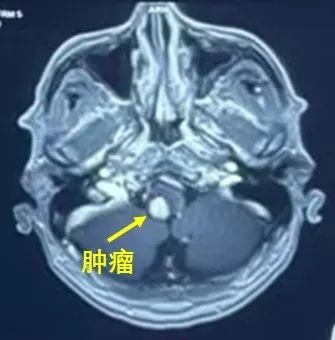

阳光讯(记者 郑亚雷 )脑干延髓作为人体的 “生命中枢”,如同掌控生命的 “总闸”,负责调节呼吸、血压、心跳等关键生命体征。由于其结构复杂、神经纤维密集,脑干恶性肿瘤成为神经外科领域极具挑战性和高风险性的疾病,被视为神经外科肿瘤操作的 “金字塔尖”—— 哪怕是微小的肿瘤压迫,都可能引发呼吸骤停、血压剧烈波动、四肢瘫痪等危及生命的症状,手术中稍有不慎便会导致严重神经功能障碍,甚至致命。

西安交大一附院神经外科团队精准攻克脑干恶性肿瘤(图1)

日前,西安交大一附院陆港院区神经外科一病区的王拓教授神经肿瘤团队,成功为一位 68 岁的脑干肿瘤患者贺某实施了延髓肿瘤完整切除术,让患者重开云电竞官方网站获健康。

西安交大一附院神经外科团队精准攻克脑干恶性肿瘤(图2)

入院后,王拓教授团队为贺某进行了详细的手术耐受性评估和脑干功能评估,制定了周密的手术预案并反复推演手术方案。同时,团队联合麻醉科、手术室神经外科团队,借助脑干电生理监测为手术保驾护航。2025 年 6 月 9 日,手术正式实施。术中,脑干电位监测多次报警,面对危机,手术团队沉着冷静、绝不放弃,在脑干电位相对平稳的间隙,于显微镜放大十数倍的视野下进行精细操作。在麻醉医生朱敦教授及电生理监测团队、手术室吴越护士长、神经外科组长张小荣等人的全力配合下,手术顺利完成,实现了延髓肿瘤的完整切除。